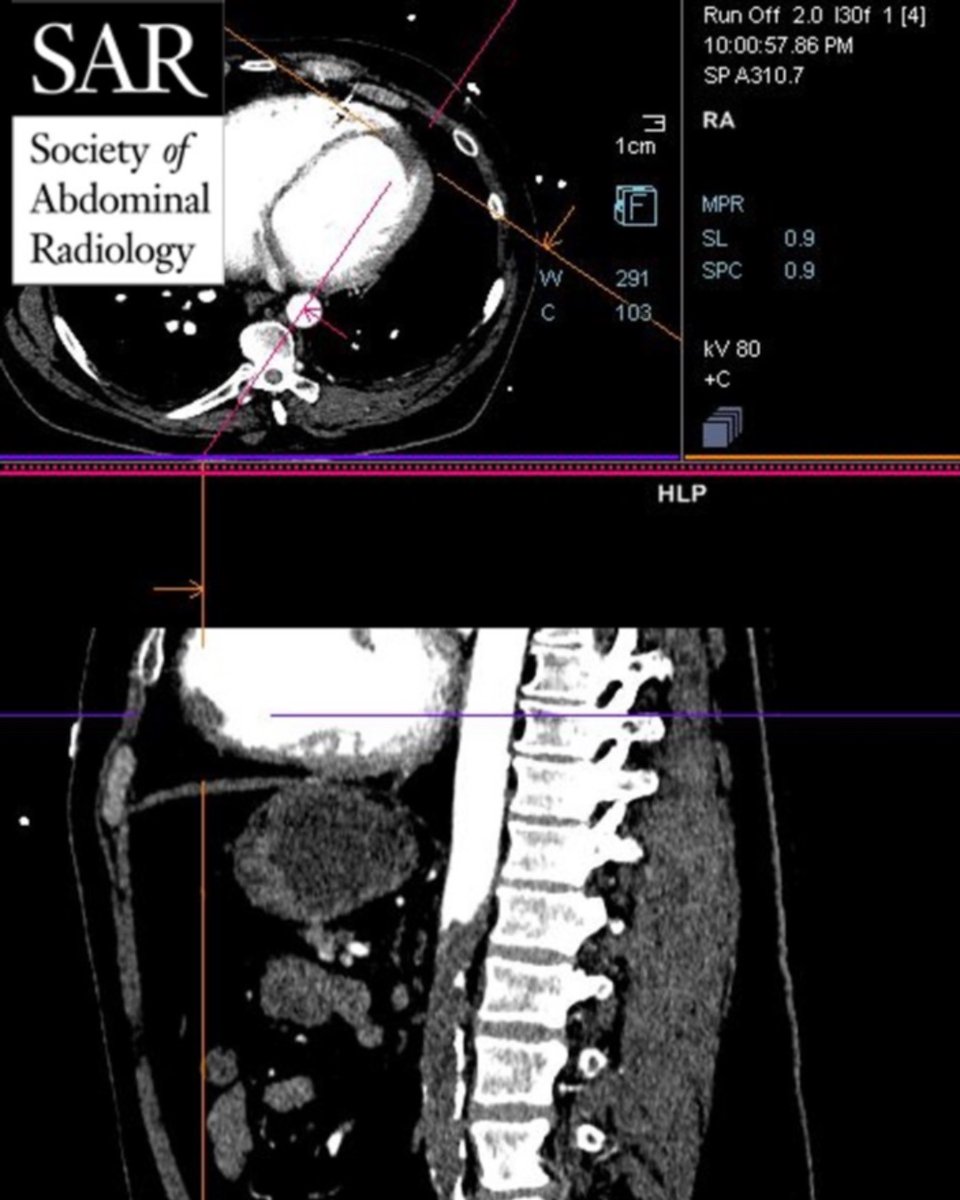

Answer for last week's case: Acute aortic occlusion (between level of SMA and renal arteries; hint was: Apparent non-contrast CT but SMA and pancreas had normal opacification and enhancement). Keep an eye out for a new challenge tomorrow.pic.twitter.com/ehKmv2YRhn